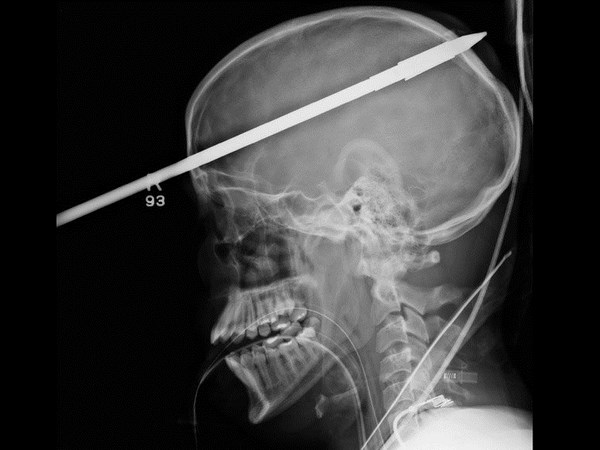

மருத்துவ உலகம் கண்டு வியந்த எக்ஸ் ரே படங்கள்

தலையில் கத்தி உள்ளது.